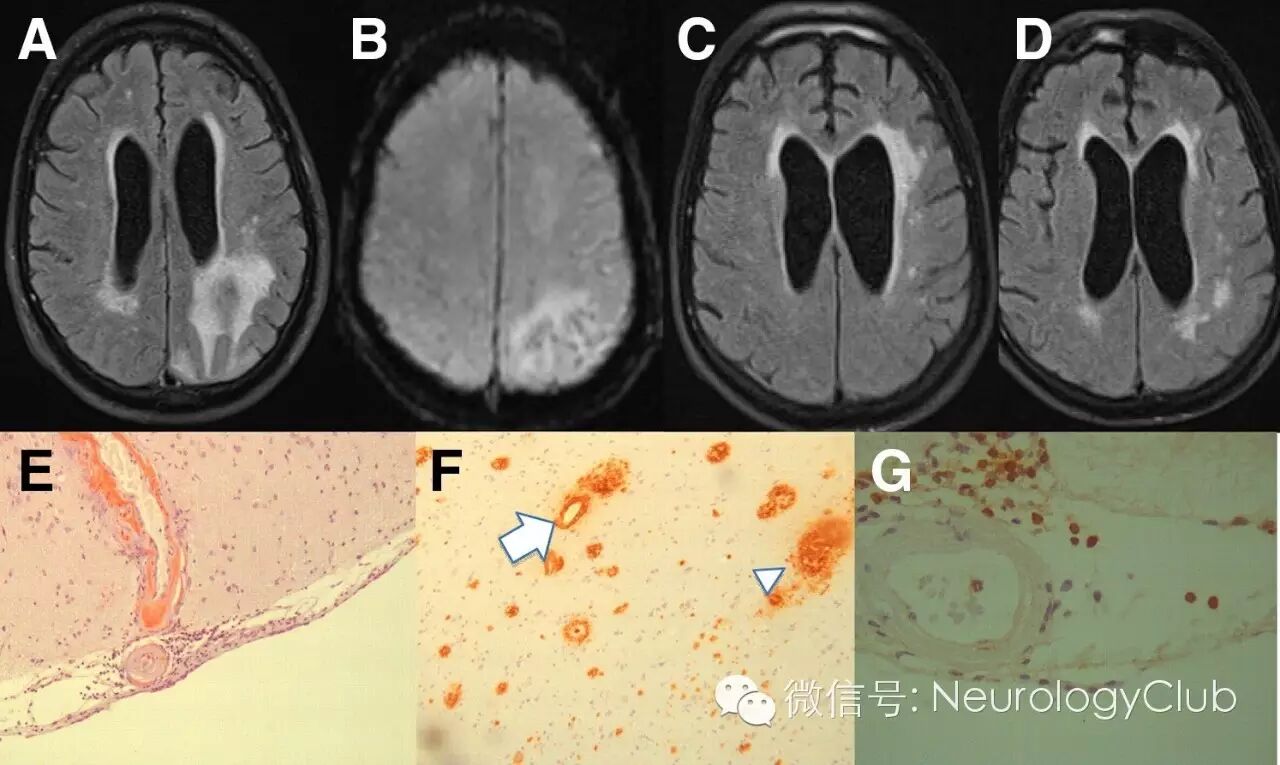

A-B:治疗前的FLAIR和T2*WI;C-D:免疫抑制治疗后FLAIR和T2*WI提示病灶明显减少;E-F:脑实质和柔脑膜血管壁淀粉样蛋白沉积[Aβ4染色,×10;刚果红染色,×10];G:柔脑膜血管周围淋巴细胞浸润[CD3染色,×10]

A-B:治疗前的FLAIR和T2*WI;C-D:免疫抑制治疗后1月复查FLAIR和T2*WI提示病灶明显减少;E:脑实质和柔脑膜血管壁淀粉样蛋白沉积[刚果红染色,×10];F:血管壁[箭]和一些淀粉样蛋白斑块[箭头,Aβ4染色,×10];G:淀粉样蛋白沉积的血管周围可见T3淋巴细胞浸润[CD3染色,×40]